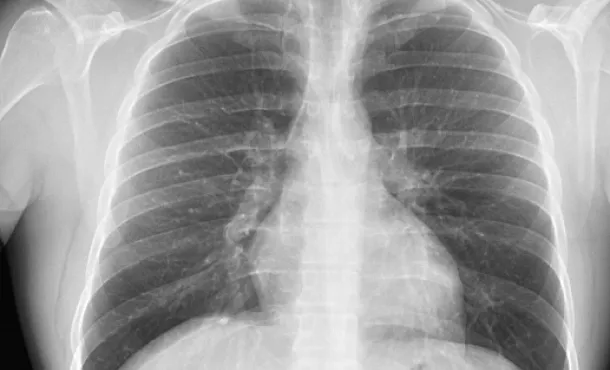

Curso de Radiografía de Tórax Interpreta imágenes, identifica estructuras y patologías respiratorias básicas. 9.8 CRÉDITOS CFC 100 HORAS

Actualización en radiología toracovascular – Cardiopatías adquiridas Curso de radiología toracovascular para médicos: diagnóstico por imagen de cardiopatías adquiridas, estructuras y patologías cardíacas. 8.6 CRÉDITOS CFC 100 HORAS